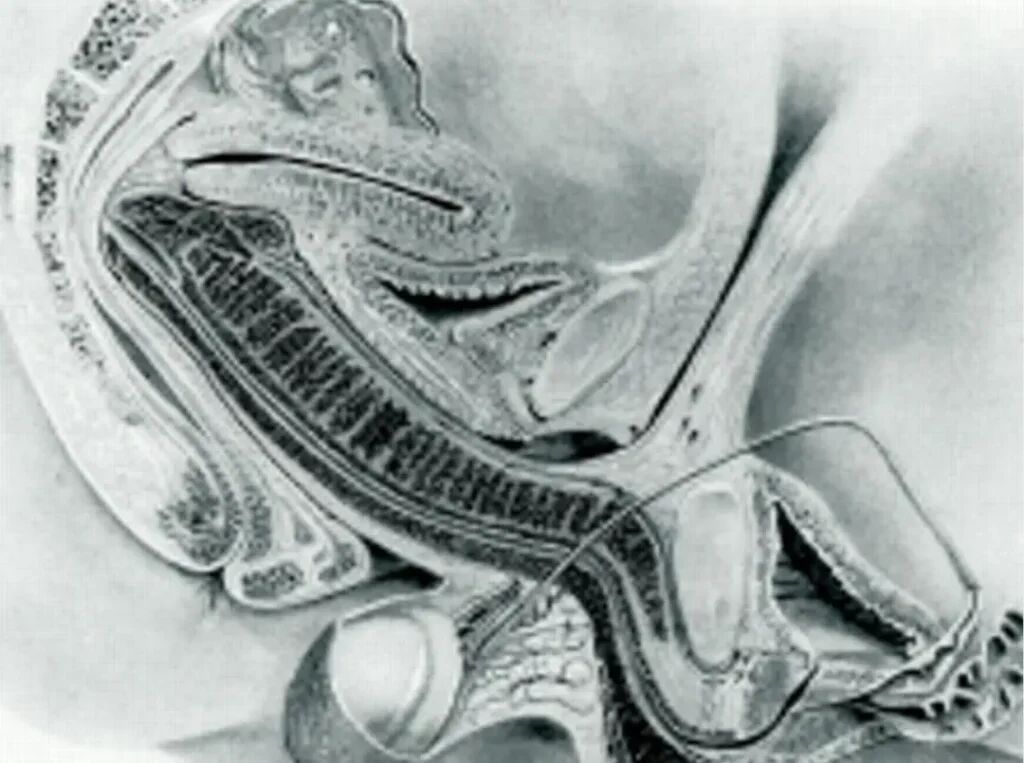

De uitkomst van het experiment was baanbrekend. Meer dan 500 jaar lang werd aangenomen dat het inwendige kanaal van het vrouwelijke voortplantingsstelsel een rechte, cilindervormige structuur had. Dat idee was gebaseerd op onder andere de anatomische schetsen van niemand minder dan Leonardo da Vinci. Indrukwekkend, maar dus niet geheel accuraat. De beelden van de scan toonden aan dat het kanaal in werkelijkheid gebogen is. Geen rechte lijn dus, maar een subtiele bocht.

Het mannelijk geslachtsdeel past zich vervolgens aan die natuurlijke kromming aan. Een eeuwenoude aanname over het vrouwelijk lichaam werd daarmee ontkracht. De beelden van het 25 jaar oude onderzoek zijn ook weer boven komen drijven, en die kun je hieronder bekijken: